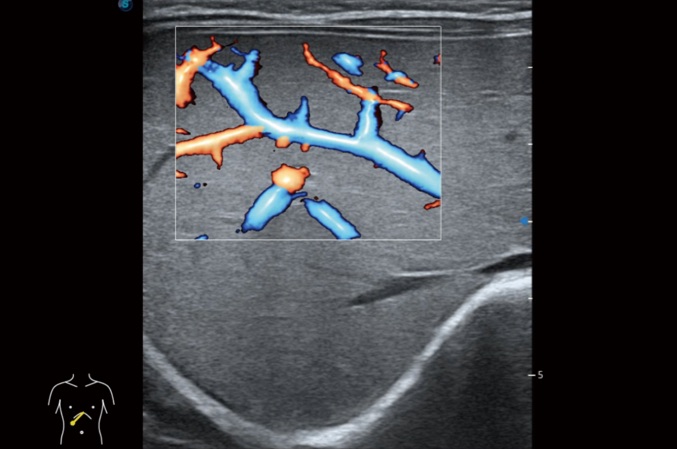

高分辨率血流成像技术提高了对低速血流信号的检测能力。在提高空间分辨率的同时,也克服了血流外溢现象,为用户提供更加真实的血流动力学信息。